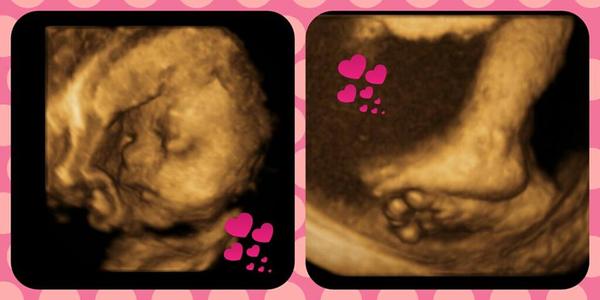

4D ultrazvuk, doporučuju

Mile maminky, pokud nektera vahate, zda jit nebo nejit na 4D ultrazvuk, tak za me jednoznacne doporucuju. Byla jsem na nem v Gennetu na Letne a nemuzu si absolutne na nic stehovat. Strasne mila asistentka, venovala se memu zazraku skoro 3/4 hod a cokoliv jsem chtela videt nebo vedet, tak ochotne ukazovala.Nejprve jsem taky vahala ( 900 Kc), ale opravdu to stoji za to. Mam z vysetreni super pocit a jeste hezci fotky. Dosud jsme nemeli vybrane jmeno a jakmile jsem videla fotku, hned jsem vedela, ktere jmeno se k ni bude hodit :D

Krásné 🙂 taky přemýšlím jestli jít nebo nejít 🙂 v kolikátém týdnu jsi byla?